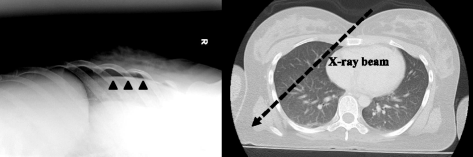

Diagnosis of pneumothorax by imaging test

All OXR was performed using mobile X-ray equipment (IME-200A, Toshiba, Tokyo, Japan) before lung US and CT scan were performed. A portable film cassette was set at 45 ° against a horizontal line in suspected hemithorax. The X-ray beams were sent vertically against the cassette over the pleural interface (Fig. 1). OXR criteria for a diagnosis of pneumothorax included a distinct visceral pleural line away from the chest wall. OXR was interpreted by an emergency radiologist (F.T.) without knowledge of other information and delineated the presence of pneumothorax.

To the best of our knowledge, this is the first study of supine OXR to detect OPX. In the primary care of trauma victims, patient movement is restricted by backboards. Upright chest radiography (CXR) is infrequently performed in the trauma bay, secondary to considerations for patient safety, especially regarding potential spine trauma and pelvic fracture. Because intrapleural air migrates into the anterior region of the pleural space (the most nondependent area) in the supine position [27], a small pneumothorax will not appear with APRX as the typical apicolateral pleural line is surrounded by intrapleural air. This means that the interface between the pneumothorax and the underlying lung is perpendicular, not parallel, to the incident x-ray beam, and cannot be easily seen. However, the x-ray beams produced by OXR could be parallel to the interface. The distribution of the intrapleural air is suitable for lung US test.